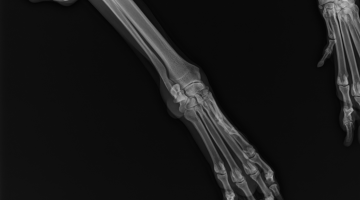

Attualmente la nostra struttura è munita di un apparecchio radiologico digitale indiretto Fuji. (Nella photogallery in basso). I vantaggi di questa tecnologia rispetto alla radiologia “analogica “ tradizionale sono molteplici. Primo fra tutti la qualità dell’immagine e la possibilità di ingrandire i particolari, correggere i contrasti, visualizzarla in negativo, ma anche misurare con precisione i dettagli. Poi la notevole riduzione dei tempi dello studio radiografico che in campo veterinario significa anche la riduzione dei tempi di anestesia del paziente con beneficio per la sua salute. Le lastre digitali non inquinano l’ambiente. Sono dei files che possono essere trasmessi per posta elettronica, masterizzati su cd o pennette di memoria da mettere nella cartella clinica da consegnare al proprietario del paziente e, nel caso della nostra struttura allegati in rete e nella scheda clinica dell’animale.